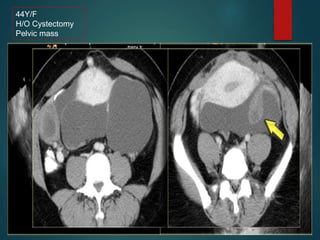

Peritoneal Inclusion Cyst…

• Multilocular peritoneal inclusion cyst/Benign cystic

mesothelioma.

• Occurs in premenopausal women with prior

gynocolical surgery or infection that results in

peritoneal scarring.

• The hormonally active ovaries secrete fluid that

becomes loculated in pelvis.

44Y/F

H/O Cystectomy

Pelvic mass

Peritoneal Inclusion Cyst… •Multilocular peritoneal inclusion cyst/Benign cystic mesothelioma. • Occurs in premenopausal women with prior gynocolical surgery or infection that results in peritoneal scarring. • The hormonally active ovaries secrete fluid that becomes loculated in pelvis.